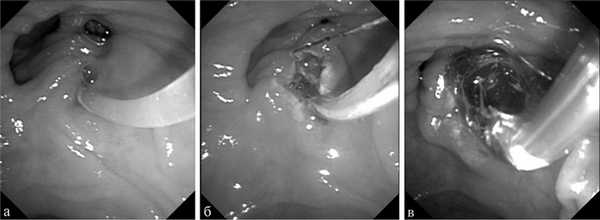

В 32 наблюдениях папиллосфинктеротомия была произведена в анамнезе, что не потребовало дорассечения на большую длину. Мы обладаем также опытом выполнения баллонной дилатации БСДК — 18 наблюдений (рис. 2). Показания к баллонной дилатации ставили при невозможности адекватной папиллосфинктеротомии для выполнения литоэкстракции и при наличии высокого риска перфорации стенки ДПК.

Рис. 2. Основные этапы доступа к общему желчному протоку с выполнением канюляционной папиллосфинктеротомии и баллонной дилатации.